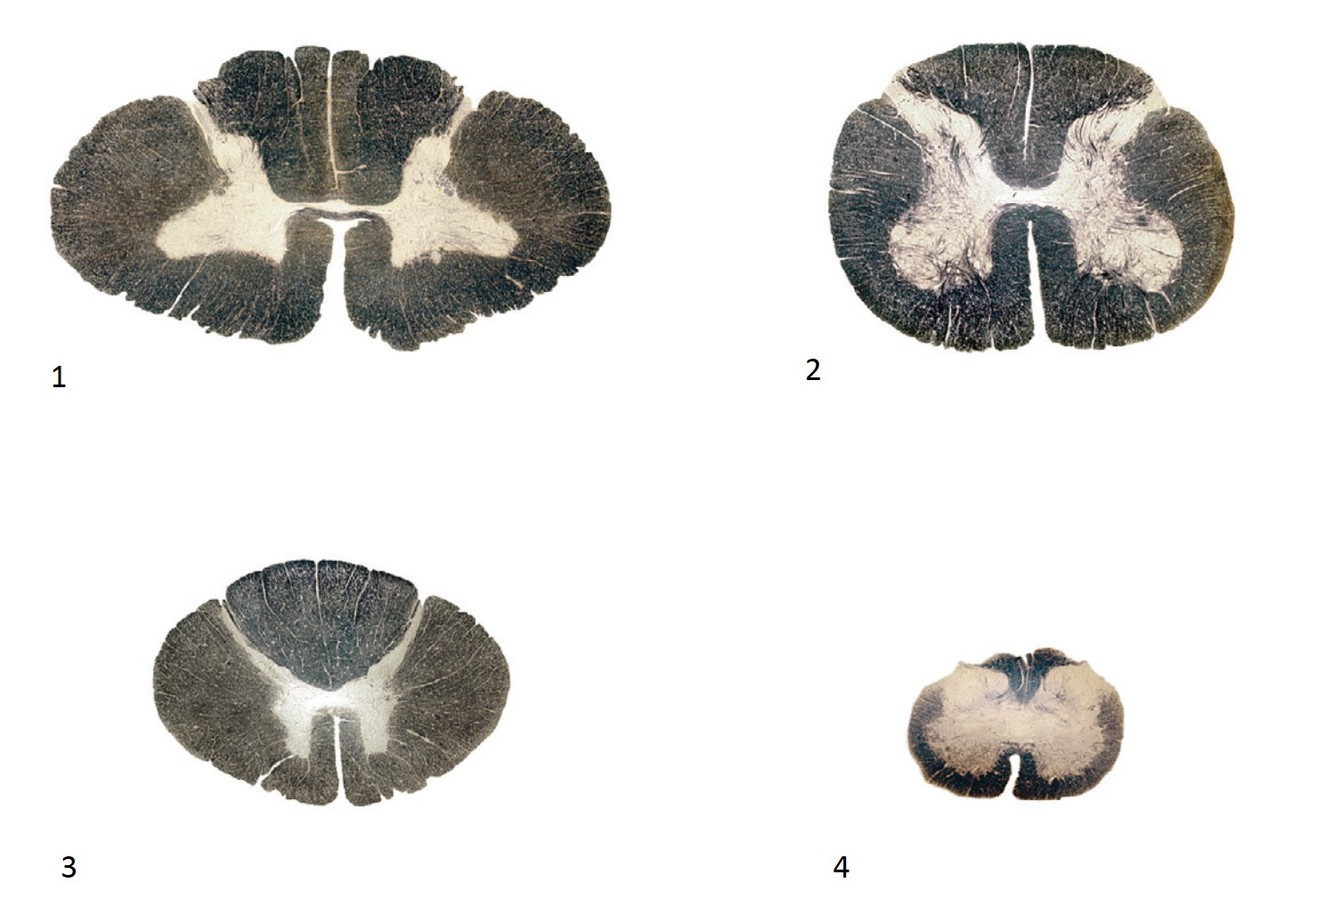

What is the correct order of spinal cord sections from cranial to caudal?

A

1, 3, 2, 4